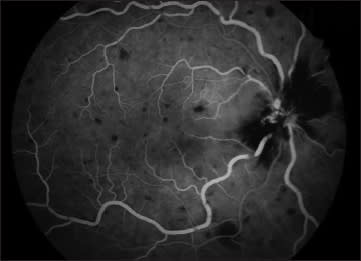

Figure 2. Fluorescein angiogram of the right eye. Blockage by intraretinal hemorrhage in the peripapillary region and hy perfluoresence in the distribution of the cilioretinal artery, indicating retinal edema.

Figure 3. Fluorescein angiogram of the right eye. Late leakage in distribution of the cilioretinal artery with venous wall staining.